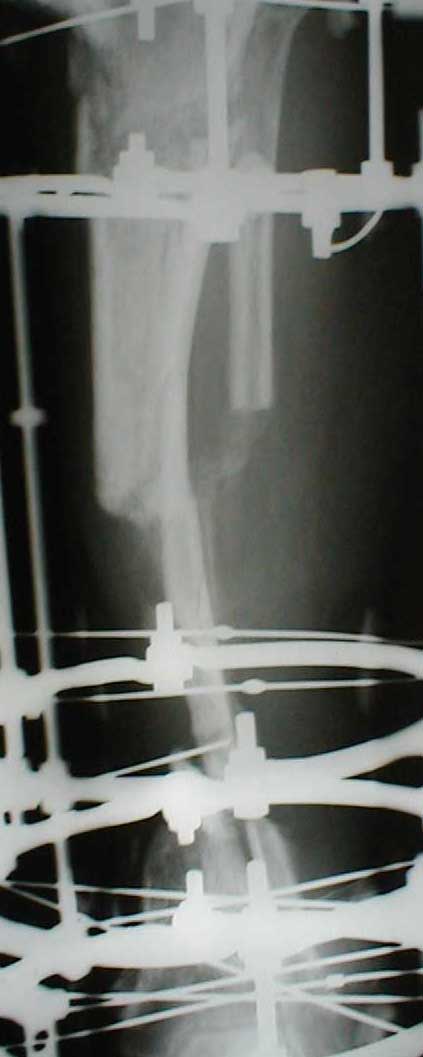

В приложении - моё наблюдение (возможно, уже представлял, тогда

извините).

Нога попала в пресс.

Ко мне больной попал черз 1,5-2 года после травмы и нескольких

операций с синегнойной инфекцией на всю голень. Меня пригласили на консультацию

насчет ампутации.

Лечил я его месяцев 8.

Малоберцовка полностью перестроилась, нога опороспособна.

При ходьбе на дальние расстояния пользуется тростью.

Осталась трофическая язва, периодически закрывается.

Один из вариантов.